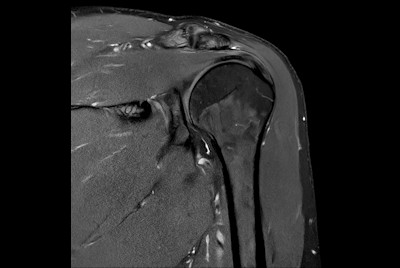

High quality Shoulder imaging with SmartSpeed Precise